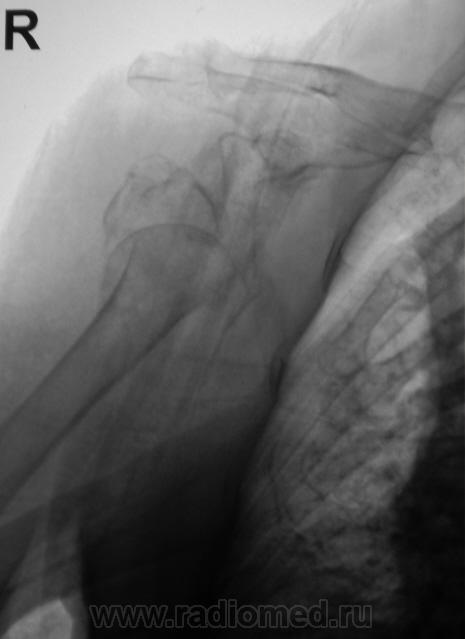

А так было до репозиции - первичный снимок.

Бесформенность между головкой и впадиной - фрагмент плечевой кости. Репозиция никакая.